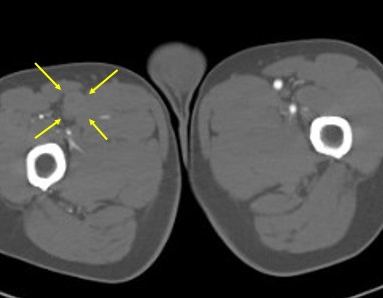

医疗组再次调阅术前CTA影像横断面:右股浅近端此区域存在血管扩张样改变(见下图)

(1)该病变的形成原因:一种考虑医源性夹层动脉瘤可能(导丝导管过该病变段时阻力大且导丝多次成袢过,下行时较为不畅);另一种考虑是否为血管本身病变引起。

4.进一步造影见右股浅动脉近端瘤样扩张,伴局部造影剂滞留现象。